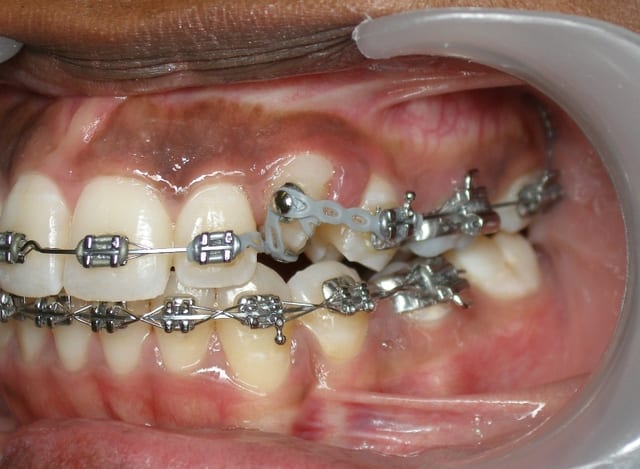

voici un cas/ jeune adulte 20ans/

collage du bouton en sous-gengival

retournement de la canine

collage br

et fin...

dsl pour la qualité du miroir...trop pourri...je l'ai renvoyé depuis.

Mais puisqu'on m'a demandé qq photos et que jsuis bien élévée...